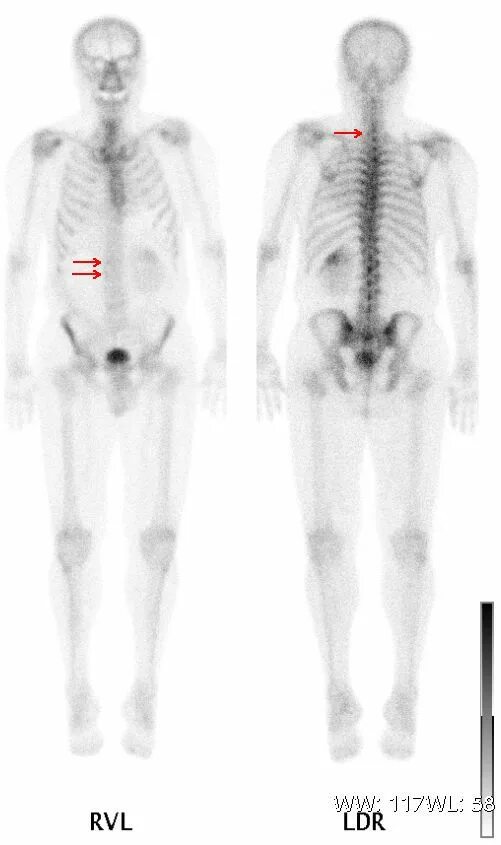

Метастазы по всему скелету